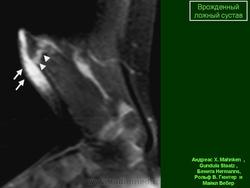

Рентгенологические признаки: щель между отломками, атрофия отломков и склероз их концов, заращение костномозгового канала (замыкающая пластинка), иногда — остеопороз.